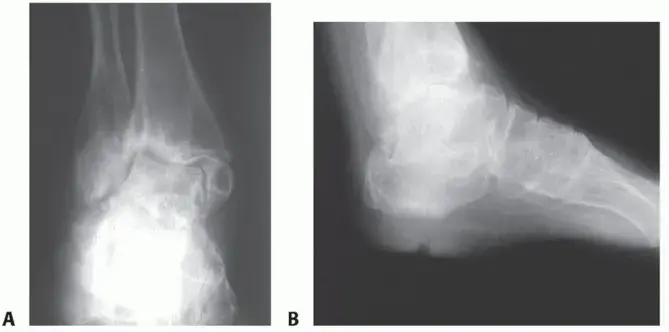

2. التهاب المفاصل التنكسي (الخشونة أو الفصال العظمي - Degenerative Arthritis / Osteoarthritis):

• ماهيته: يُعرف أيضًا باسم "خشونة المفاصل"، وهو النوع الأكثر شيوعًا من التهاب المفاصل. يحدث عندما يتآكل الغضروف الواقي الذي يغطي نهايات العظام بمرور الوقت، مما يؤدي إلى احتكاك العظام ببعضها البعض.

• تأثيره على اليد: غالبًا ما يؤثر التهاب المفاصل التنكسي على المفاصل السلامية القريبة (PIP) والبعيدة (DIP) بشكل أكبر من المفاصل السنعية السلامية (MCP).

• أسبابه: قد ينشأ بشكل مجهول السبب (دون سبب واضح)، أو قد يحدث بعد إصابة سابقة (مثل كسر أو التواء)، أو نتيجة لعدوى سابقة في المفصل. العوامل الوراثية والتقدم في العمر والإجهاد المتكرر للمفاصل تزيد من خطر الإصابة.

4. إصابات أو رضوض سابقة: أي كسر أو التواء شديد أو خلع في مفاصل اليد قد يؤدي إلى تلف الغضروف ويؤهل لظهور خشونة المفاصل لاحقًا في الحياة، حتى بعد سنوات من الإصابة الأولية.

• تشوهات المفاصل: مع تقدم المرض، يمكن أن تتغير المفاصل في شكلها، فتظهر عليها نتوءات عظمية أو انحرافات في الأصابع (مثل الانحراف الزندي في الروماتويد، أو تشوهات عنق البجعة أو العروة في الأصابع).

• صوت طقطقة أو احتكاك: قد يسمع المريض أو يشعر بصوت طقطقة أو احتكاك عند تحريك المفصل، وهو دليل على تآكل الغضروف واحتكاك العظام.